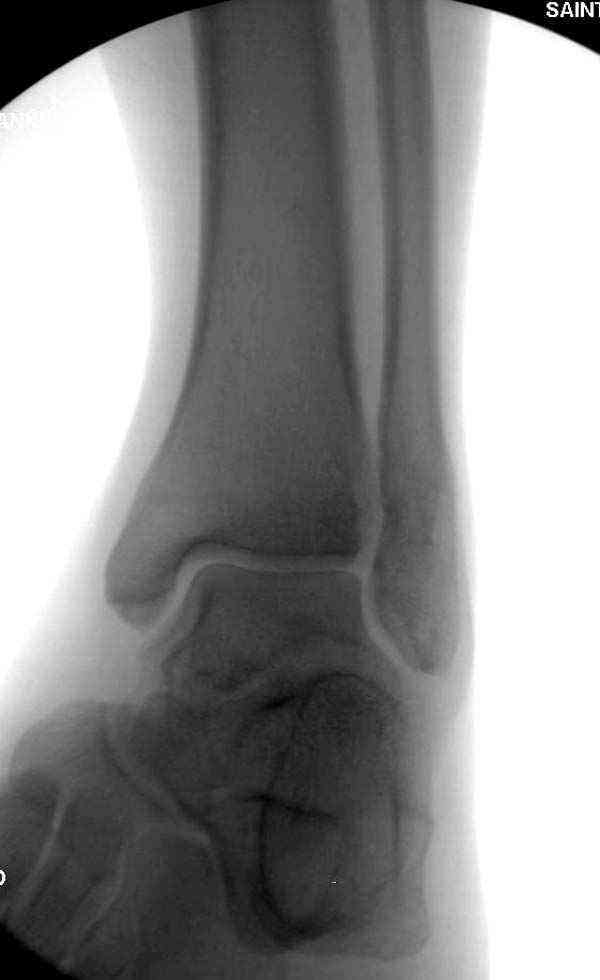

Нет первичных снимков, перелом очень низкий и под большим сомнением диагноз разрыва синдесмоза. Медиальная сторона отрепонирована на "хорошо" и, по-видимому, прорезание проволоки произошло во время операции. Без снимков трудно судить о высоте малоберцовой, а лодыжка находится в варусе. Лагирование получилось, но возле тонких шурупов передне-задний шуруп выглядит немного тяжеловато.

Коллеги правы, что при рутинных переломах достаточным бывает обычные снимки с мортизом. А стрессовые рентгенограммы могут уточнить, есть ли разрыв синдесмоза.

Здесь несколько частных случаев: перелом голеностопа со сравнительными снимками и разрыв синдесмоза, а также медиальная Hook пластина.